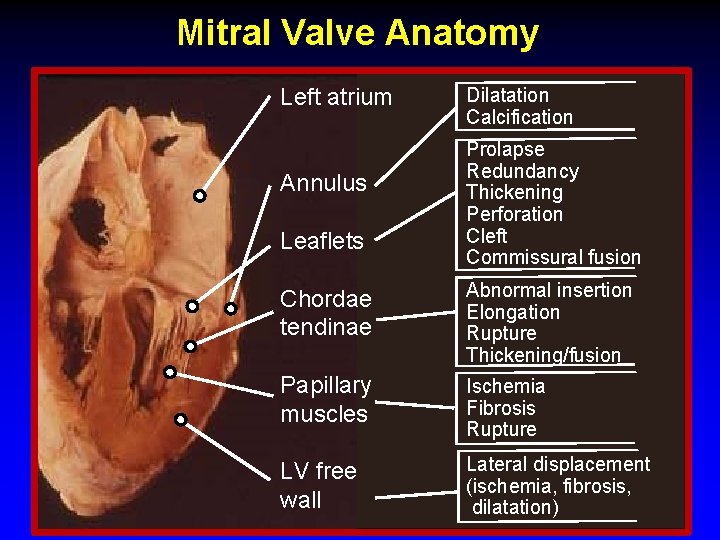

Mitral Valve Anatomy Dilatation Left atrium Annulus Leaflets Dilatation Calcification Prolapse Redundancy Thickening Perforation Cleft Commissural fusion Chordae tendinae Abnormal insertion Elongation Rupture Thickening/fusion Papillary muscles Ischemia Fibrosis Rupture LV free wall Lateral displacement (ischemia, fibrosis, dilatation)